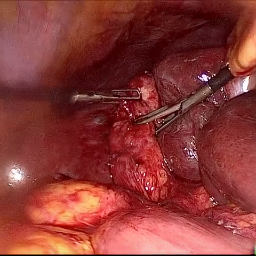

Refer to caption (a) Input Refer to caption (b) DIACMPN Refer to caption (c) Desmoke-LAP Refer to caption (d) PFAN Refer to caption (e) MITNET Refer to caption (f) Salazar Refer to caption (g) Dehamer Refer to caption (h) Ours Refer to caption (i) Target

Figure 2: Comparison of different methods on the DesmokeData dataset.

IV-C2 Qualitative Analysis

Figures 3 and 2 provide a visual comparison of the desmoking results on challenging images from the test sets. The visual results corroborate our quantitative findings. DCP not only fails to remove the dense smoke but also introduces severe color distortion. CNN-based methods like FFA-Net and MSBDN successfully remove a large portion of the smoke but tend to either leave behind a thin layer of residual haze or over-smooth the image, losing critical textural details of the tissue and surgical instruments. The Transformer-based methods, DehazeFormer and PFAN, produce significantly better results by restoring more details. However, they can sometimes struggle with non-uniform smoke distribution, resulting in regions with unnatural brightness or minor artifacts.

In stark contrast, our RGA-Net generates visually superior results that are remarkably close to the ground-truth images. It effectively removes even the densest plumes of smoke while simultaneously preserving fine-grained details, such as blood vessels, tissue textures, and reflections on surgical tools. Furthermore, the color and illumination of the restored scene appear more natural and consistent, which is a direct benefit of our model’s ability to handle both local and global features through its hybrid attention and cross-gating mechanisms. This enhanced visual clarity is crucial for improving the surgeon-robot interface in real-world clinical applications.